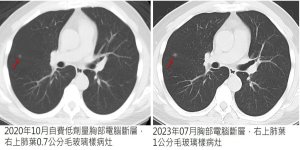

小點點,大學問---肺部結節的影像密碼

肺部結節是胸腔外科門診最常見、也最讓人不安的影像發現。實際上,超過九成的結節都是良性的,但面對影像上那顆「小點點」,如何判斷風險、決定追蹤或治療,是醫療團隊與病患共同面臨的重要課題。